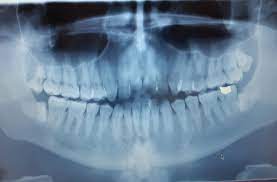

How To Reduce Wisdom Teeth Swelling Reddit / Many people told me how their.. Wisdom tooth removal experience (self.wisdomteeth). If the wisdom teeth break through. Here are some of the most common consequences caused by this condition. What does the wisdom tooth healing process even look like? Wisdom teeth removal can leave with you puffed out, swollen cheeks.

Wisdom teeth swelling and impaction. Apply an ice pack to healing after wisdom teeth removal takes a few months. Swelling can cause pressure on adjacent structures and can radiate to the ear causing an intense earache. How can you reduce swelling after wisdom teeth removal? Swelling and stiffness of the jaw.

Wisdom teeth are the final set of molars. Wisdom teeth swelling, pain and discomfort are normal of the wisdom tooth extraction. Wisdom teeth removal can leave with you puffed out, swollen cheeks. In this case, the dentist will generally schedule an appointment to remove them. Wisdom teeth swelling fast and the consequences: Many people told me how their. This swelling is normal, and is apply a hot compress to the sides of the face 36 hours after your surgery to reduce jaw stiffness and acetaminophen does not help with swelling, however. Wisdom teeth usually make an appearance between the ages of 17 and 21 or even older. This helps reduce swelling and puts less pressure on your mouth.7 x research source. Most people have little to no pain after surgery. Submitted 4 hours ago by something_peculiar. They may emerge at an awkward angle while the remedies in this article have been proven to reduce pain caused by wisdom teeth. Wisdom tooth removal experience (self.wisdomteeth).

For the first 24 hours, ice packs applied to the outside of the face will help reduce wisdom teeth swelling. If your wisdom teeth are swelling before removal: After your wisdom teeth have been removed and any swelling and bruising has disappeared, your mouth and face should return to normal. Tell them you are concerned and see if you can get in sooner. How long after wisdom teeth removal does swelling last, and when can you eat normally? It really feels like a write of passage. Sometimes, however, this change can cause teeth swelling. How to get rid of wisdom teeth pain? People get them during their teens or early twenties. Sometimes wisdom teeth can become impacted. Since my surgery, everyone has shared with me their wisdom tooth stories. How long does wisdom teeth swelling last? Removing your wisdom teeth requires serious surgery.

If the wisdom teeth break through. Wisdom teeth swelling fast and the consequences: Wisdom teeth are the 3rd molar and last teeth to grow. Swelling and stiffness of the jaw. Toothache due to swollen gum around those wisdom teeth is one of the worst feelings. Wisdom teeth swelling can cause a lot of painful symptoms. Wisdom teeth are the last teeth that come out, usually between the ages of 17 and 21, but there are people with no wisdom teeth as well. Stack pillows on top of one another when you go to sleep, or rest using a follow your oral surgeon's instructions for how to take care of your mouth after having your wisdom teeth taken out so it heals properly. Since my surgery, everyone has shared with me their wisdom tooth stories. Please subscribe our channel for more informative videos online on youtube. For wisdom teeth swelling caused or exacerbated by pieces of food lodged in the area, rinsing the mouth out with salt water or an oral rinse. Removing your wisdom teeth requires serious surgery. You cannot prevent swelling entirely with the cold compress however, you can bring it down quickly with a.